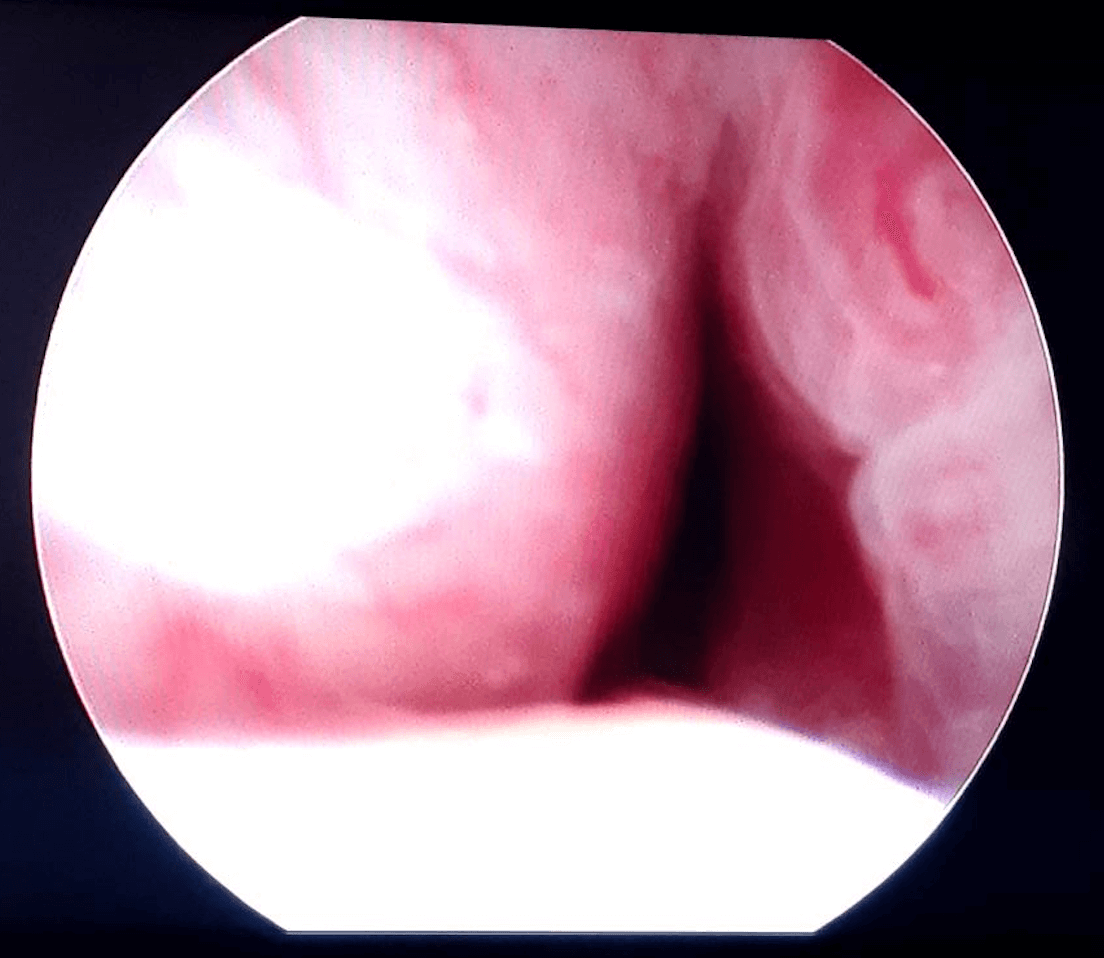

Before & After Pics of UroLift in Atlanta

Procedure